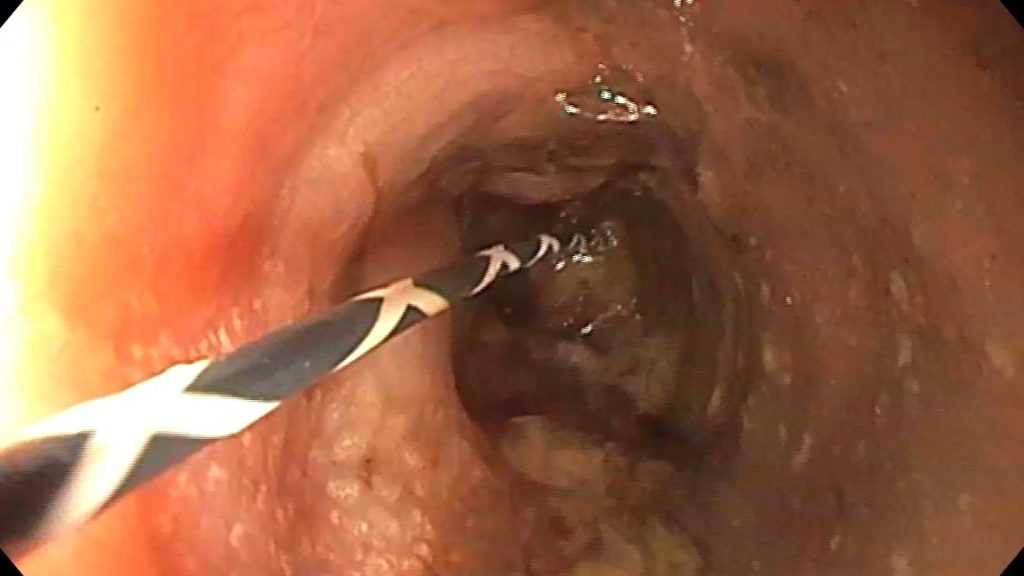

Cazul lunii

Over-the-scope-clip duodenal

Bărbat in vârstă de 70 de ani, internat pentru vărsături și diaree, simptome debutate cu 24h anterior prezentării. Fără dureri abdominale, fără febra sau frisoane. Istoricul medical descrie fibrilație atrială si mutație a protrombinei cu multiple episoade de embolie pulmonara (tratament cu Acenocumarol la domiciliu); insuficienta cardiaca cronica; hipertensiune arteriala; hipertensiune pulmonara; proteza de genunchi drept cu multiple intervenții chirurgicale, inclusiv episod de sepsis – tratament cronic antibiotic la domiciliu (Amoxicilină + Tetraciclină); tulburare neurocognitivă.